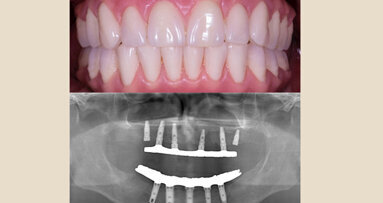

El experto dominicano en estética dental, Rony Joubert, explica de forma simple y sencilla la rehabilitacion del paciente edéntulo con una prótesis híbrida cerámica.

La prótesis fijas sobre implantes dentales osteointegrados pueden ser de tipo cementadas o atornilladas. En el caso de las prótesis totales atornilladas, predominan las llamadas prótesis híbridas (plásticas o cerámicas), donde con la estructura protésica podemos crear los tejidos blandos perdidos, así como reponer los dientes ausentes.

Las ventajas de estas estructuras cerámicas son: su resistencia y duralidad, su alta estética y estabilidad de color a través del tiempo, su excelente función masticatoria, entre otras. Sin embargo, estas prótesis tienen limitantes importantes como: son complejas de fabricar, difícil de reparar, costosas.

En líneas generales, se colocan entre 4 y 5 implantes en la arcada inferior y 5 o más en la superior, buscando asentar fijaciones de más de 10 milímetros de longitud con diámetros que varíen entre 3.3 y 4.2 milímetros. Los mismos debería estar distribuidos generando el mejor polígono de sustentación posible, y salvando las estructuras anatómicas nobles del área (dentario inferior y seno maxilar superior). El paralelismo entre los implantes debería ser adecuado, aunque algunas técnicas preconizan la posibilidad de colocarlos angulados (ejemplo All-on-4, 5 ó 6), de forma que se pueda proteger órganos importantes. Si la distribución y ferulización de los implantes es adecuada, se permiten pónticos a extensión distal de hasta de 13 milímetros sin que se comprometa la biomecánica del aparato.